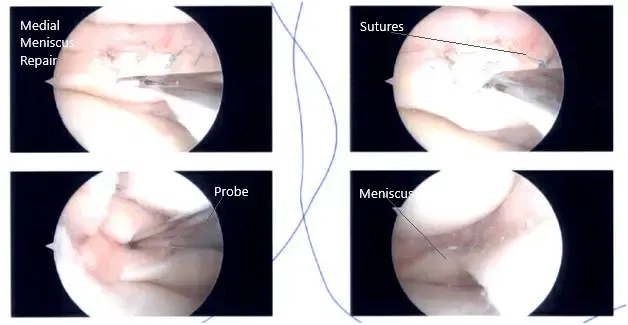

A lateral entry portal was established, and the knee joint was examined. A peripheral tear of the medial meniscus was found. A grade 1 to grade 2 osteochondral lesion of the medial condyle of the femur was also found. The ACL had some fraying and degeneration.

There was no lesion on the meniscus or lateral femur and condyle. The patellofemoral joint was inspected and found to be good. Now, the repair of the medial meniscus was performed. FasT-Fix sutures were used. Seven sutures were used to fix the peripheral tear from the posterior horn to the midbody.

Gross fixation and stability of the meniscus was found to be satisfactory. Final arthroscopic pictures were taken. The knee was lavaged with copious normal saline. The wound was closed